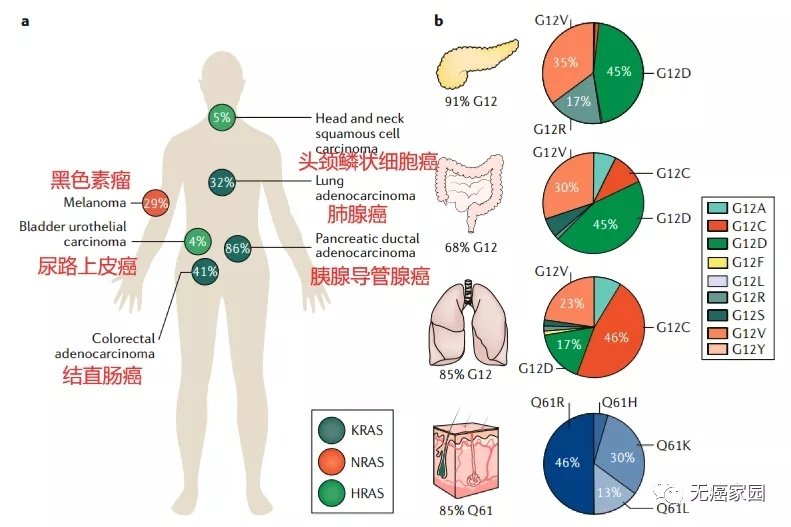

针对KRAS G12C 突变癌症的新型疗法获得突破性药物

针对KRAS G12C 突变癌症的新型疗法获得突破性药物

美国食品药品监督管理局 (FDA) 已授予 D3S-001 突破性疗法认定,用于治疗KRAS G12C 突变的局部晚期或转移性非小细胞肺癌...